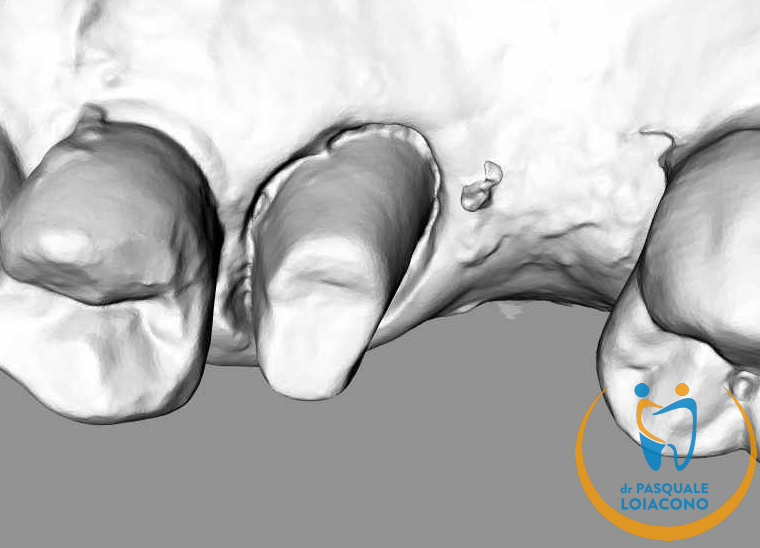

Dalla scansione intraorale al manufatto protesico finito, servizio chiavi in mano